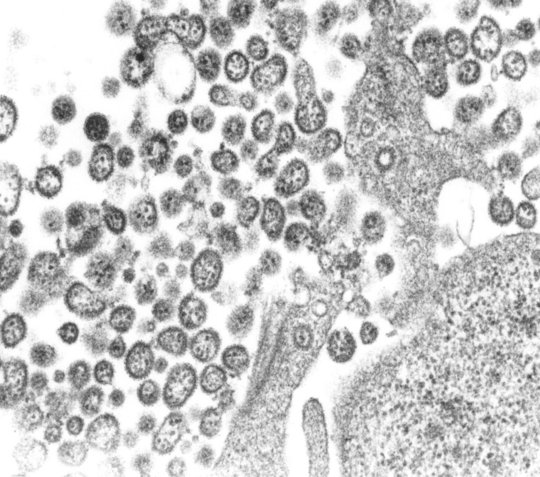

Das Lassa-Virus wurde erstmals im Jahr 1969 isoliert und nach seinem Entdeckungsort, der Stadt Lassa, im Nordosten Nigerias, benannt. Es gehört zur Gruppe der Arenaviren und wird zu den hämorrhagischen Fieberviren gezählt. Infektionen mit dem Lassa-Virus erzeugen starke grippeähnliche Symptome mit Fieber, Durchfall und Erbrechen. In schweren Fällen kann die Infektion zur Blutungsneigung und zum Tod führen. Das Lassa-Virus wird von Vielzitzenmäusen (Mastomys natalensis) über Ausscheidungsprodukte wie Urin auf den Menschen übertragen (Zoonose). Als Schmierinfektion über kontaminierte Nahrung oder über Virus-haltige Staubpartikel kann der Erreger auf den Menschen und anschließend von Mensch zu Mensch übertragen werden.